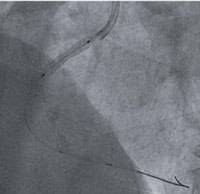

この血管撮影装置は、血管内に細い管(カテーテル)を挿入し、造影剤を注入することで、心臓を栄養している冠動脈の狭窄(狭心症)や閉塞(心筋梗塞)を診断します。

さらに、検査からすぐさま狭心症の風船治療など、緊急治療への対応も可能な装置です。

右冠動脈の狭窄

ステント挿入術中

治療後